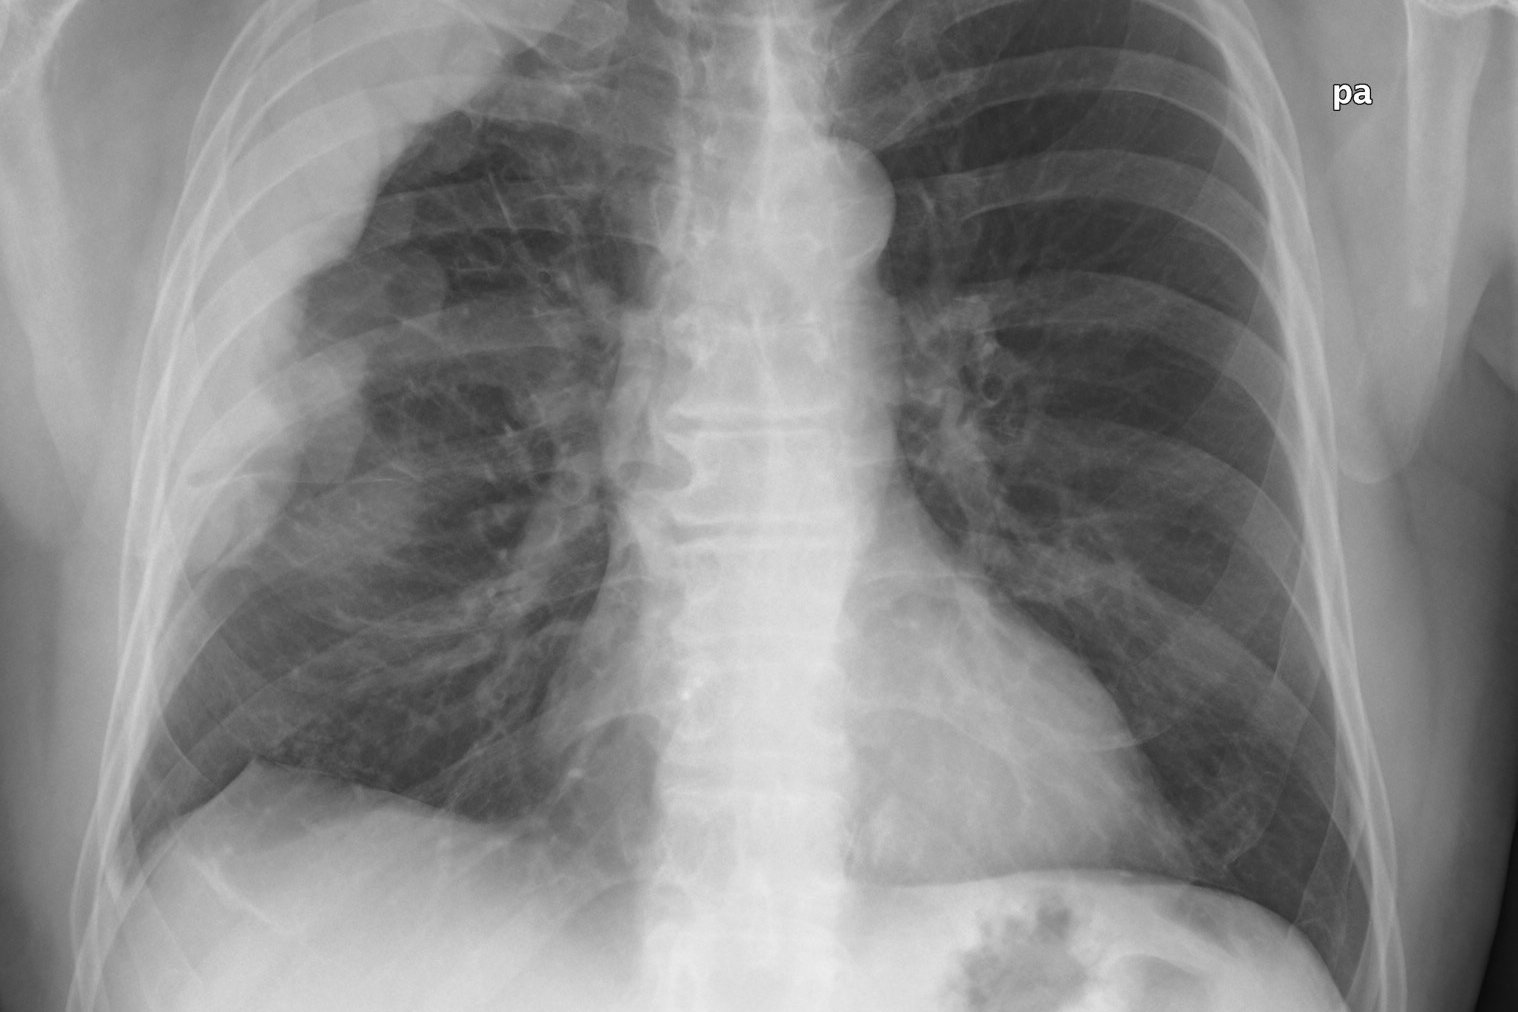

(Wien, 16-05-2018) Ein Krebsmedikament zeigt in präklinischen Modellen vielversprechende Wirksamkeit bei der Wachstumshemmung des malignen Pleuramesothelioms, einem tödlich verlaufenden Tumor des Rippenfells. Dies ist das Ergebnis einer neuen Studie, die von der MedUni Wien gemeinsam mit ForscherInnen aus Deutschland und Ungarn veröffentlicht wurde.

Das maligne Pleuramesotheliom ist ein besonders aggressiver Tumor, der von Zellen des Rippenfells ausgeht. Er entsteht typischerweise durch vorangegangene Asbestbelastung. Die Standardbehandlung des Mesothelioms umfasst Chirurgie, Chemotherapie, Bestrahlung oder eine übergreifende Therapie, bei der diese Ansätze kombiniert werden. Da diese konventionellen Therapien die Grenze ihrer Wirksamkeit erreicht haben, werden zur Verbesserung der Überlebenschancen neue zielgerichtete Ansätze gesucht.